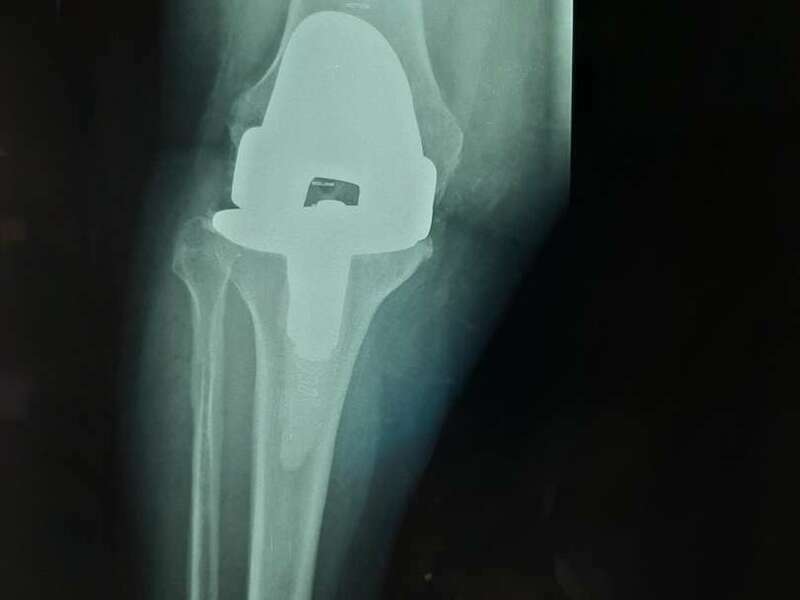

Cas 2. Luxation intra-prothétique de PTH

Si la tête fémorale prothétique se sépare de la tige fémorale, on parle de luxation intra-prothétique. Dans ce cas-là, réduction doit se faire à ciel ouvert avec le repositionnement de nouveaux implants identiques aux premiers.